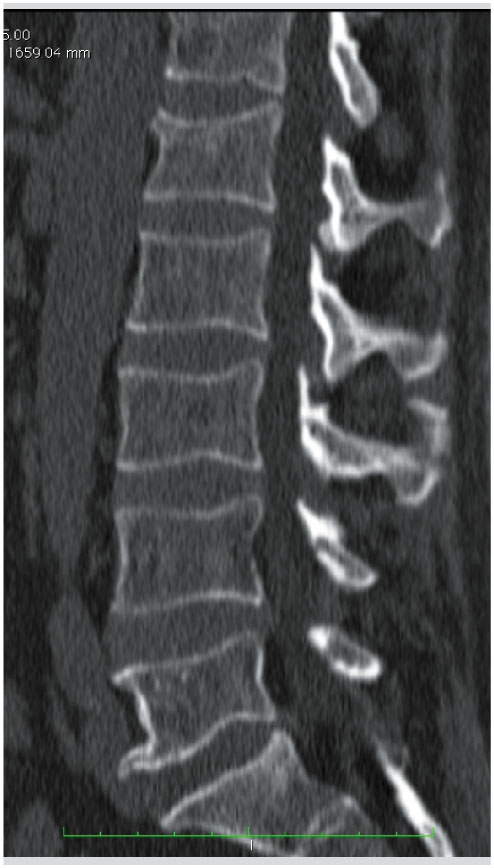

Reformations Sagittale A Et Coronale B D Une Tomodensitometrie Du Download Scientific Diagram

Prise En Charge Des Fractures A Haute Et Basse Energie Traumatique De La Colonne Thoracique Et Lombaire Revue Medicale Suisse

Fracture Du Corps Vertebral Fracture D Une Vertebre